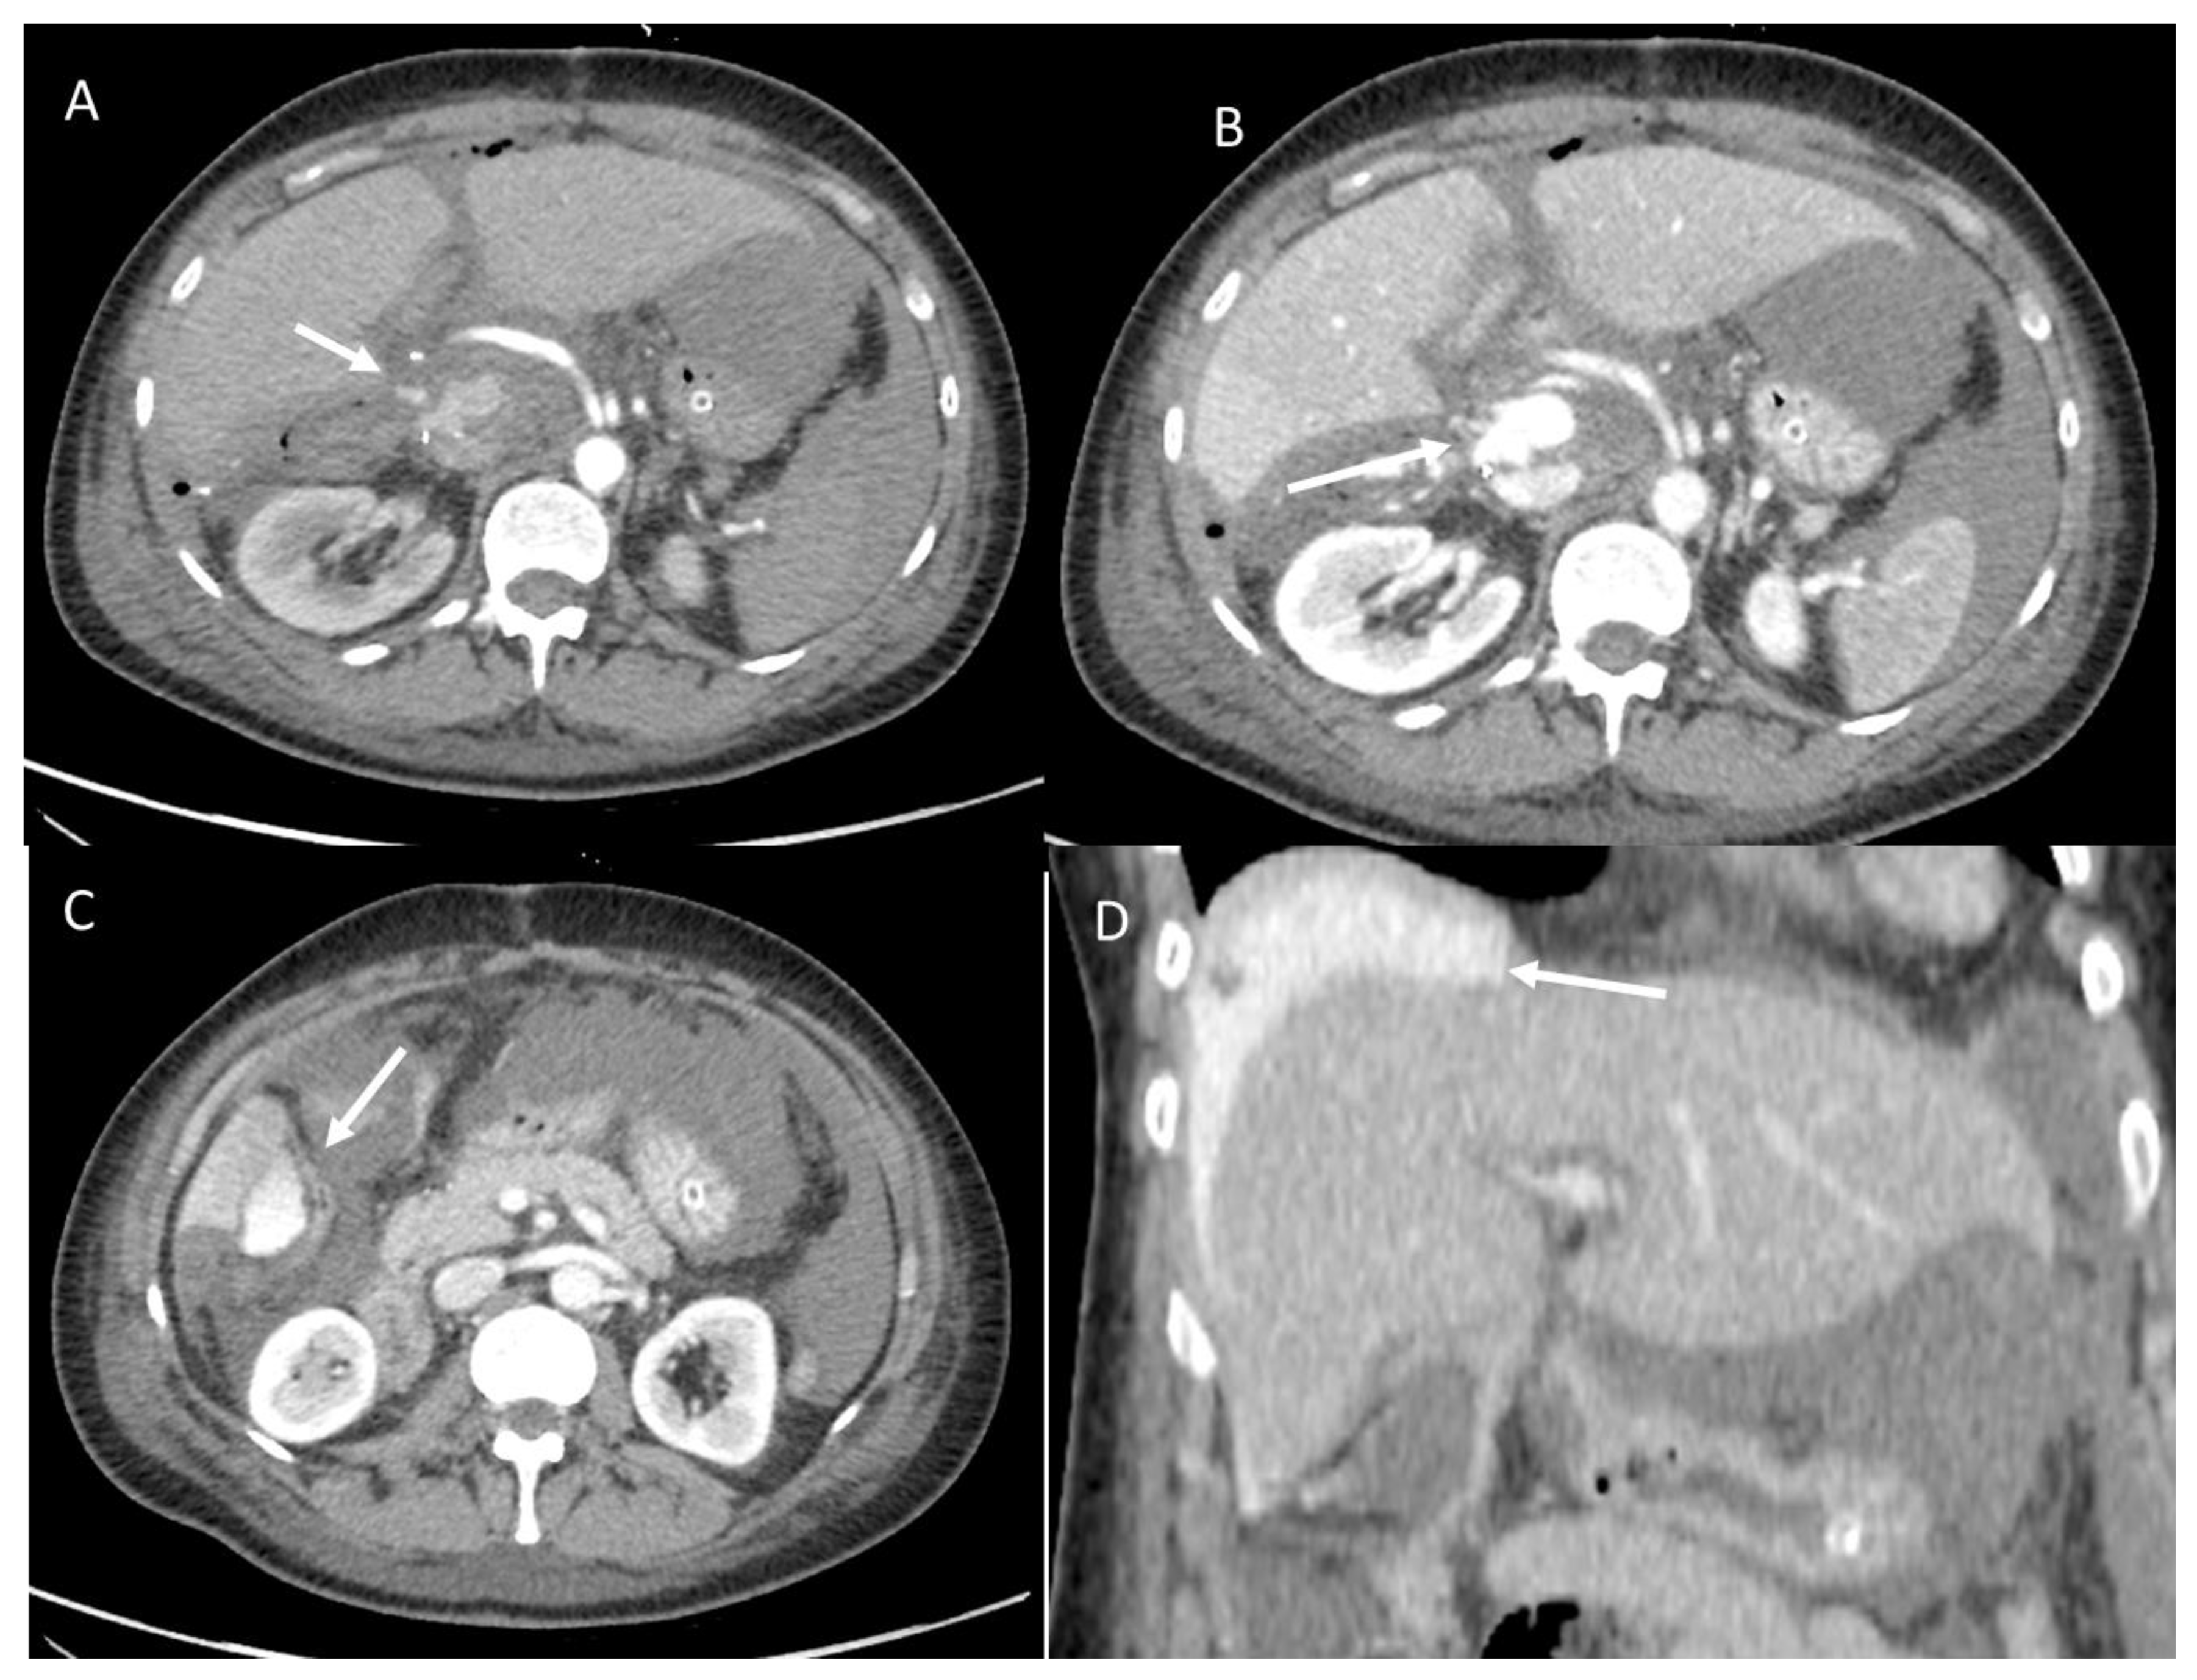

3.1.2. Posthepatectomy Hemorrhage

- Rahbari, N.N.; Garden, O.J.; Padbury, R.; Maddern, G.; Koch, M.; Hugh, T.J.; Fan, S.T.; Nimura, Y.; Figueras, J.; Vauthey, J.N.; et al. Post-hepatectomy haemorrhage: A definition and grading by the International Study Group of Liver Surgery (ISGLS). HPB 2011, 13, 528–535. [Google Scholar] [CrossRef] [PubMed]

- Lubner, M.; Menias, C.; Rucker, C.; Bhalla, S.; Peterson, C.M.; Wang, L.; Gratz, B. Blood in the belly: CT findings of hemoperitoneum. Radiographics 2007, 27, 109–125. [Google Scholar] [CrossRef] [PubMed]

- Ilyas, M.; Bashir, M.; Robbani, I.; Rasool, S.R.; Shera, F.A.; Hamid, I. Sentinel clot sign in hemoperitoneum. Abdom. Radiol. 2019, 44, 1955–1956. [Google Scholar] [CrossRef]

- Shanmuganathan, K.; Mirvis, S.E.; Reaney, S.M. Pictorial review: CT appearances of contrast medium extravasations associated with injury sustained from blunt abdominal trauma. Clin. Radiol. 1995, 50, 182–187. [Google Scholar] [CrossRef] [PubMed]

- Byun, J.; Kim, K.W.; Lee, J.; Kwon, H.J.; Kwon, J.H.; Song, G.W.; Lee, S.G. The role of multiphase CT in patients with acute postoperative bleeding after liver transplantation. Abdom. Radiol. 2020, 45, 141–152. [Google Scholar] [CrossRef]